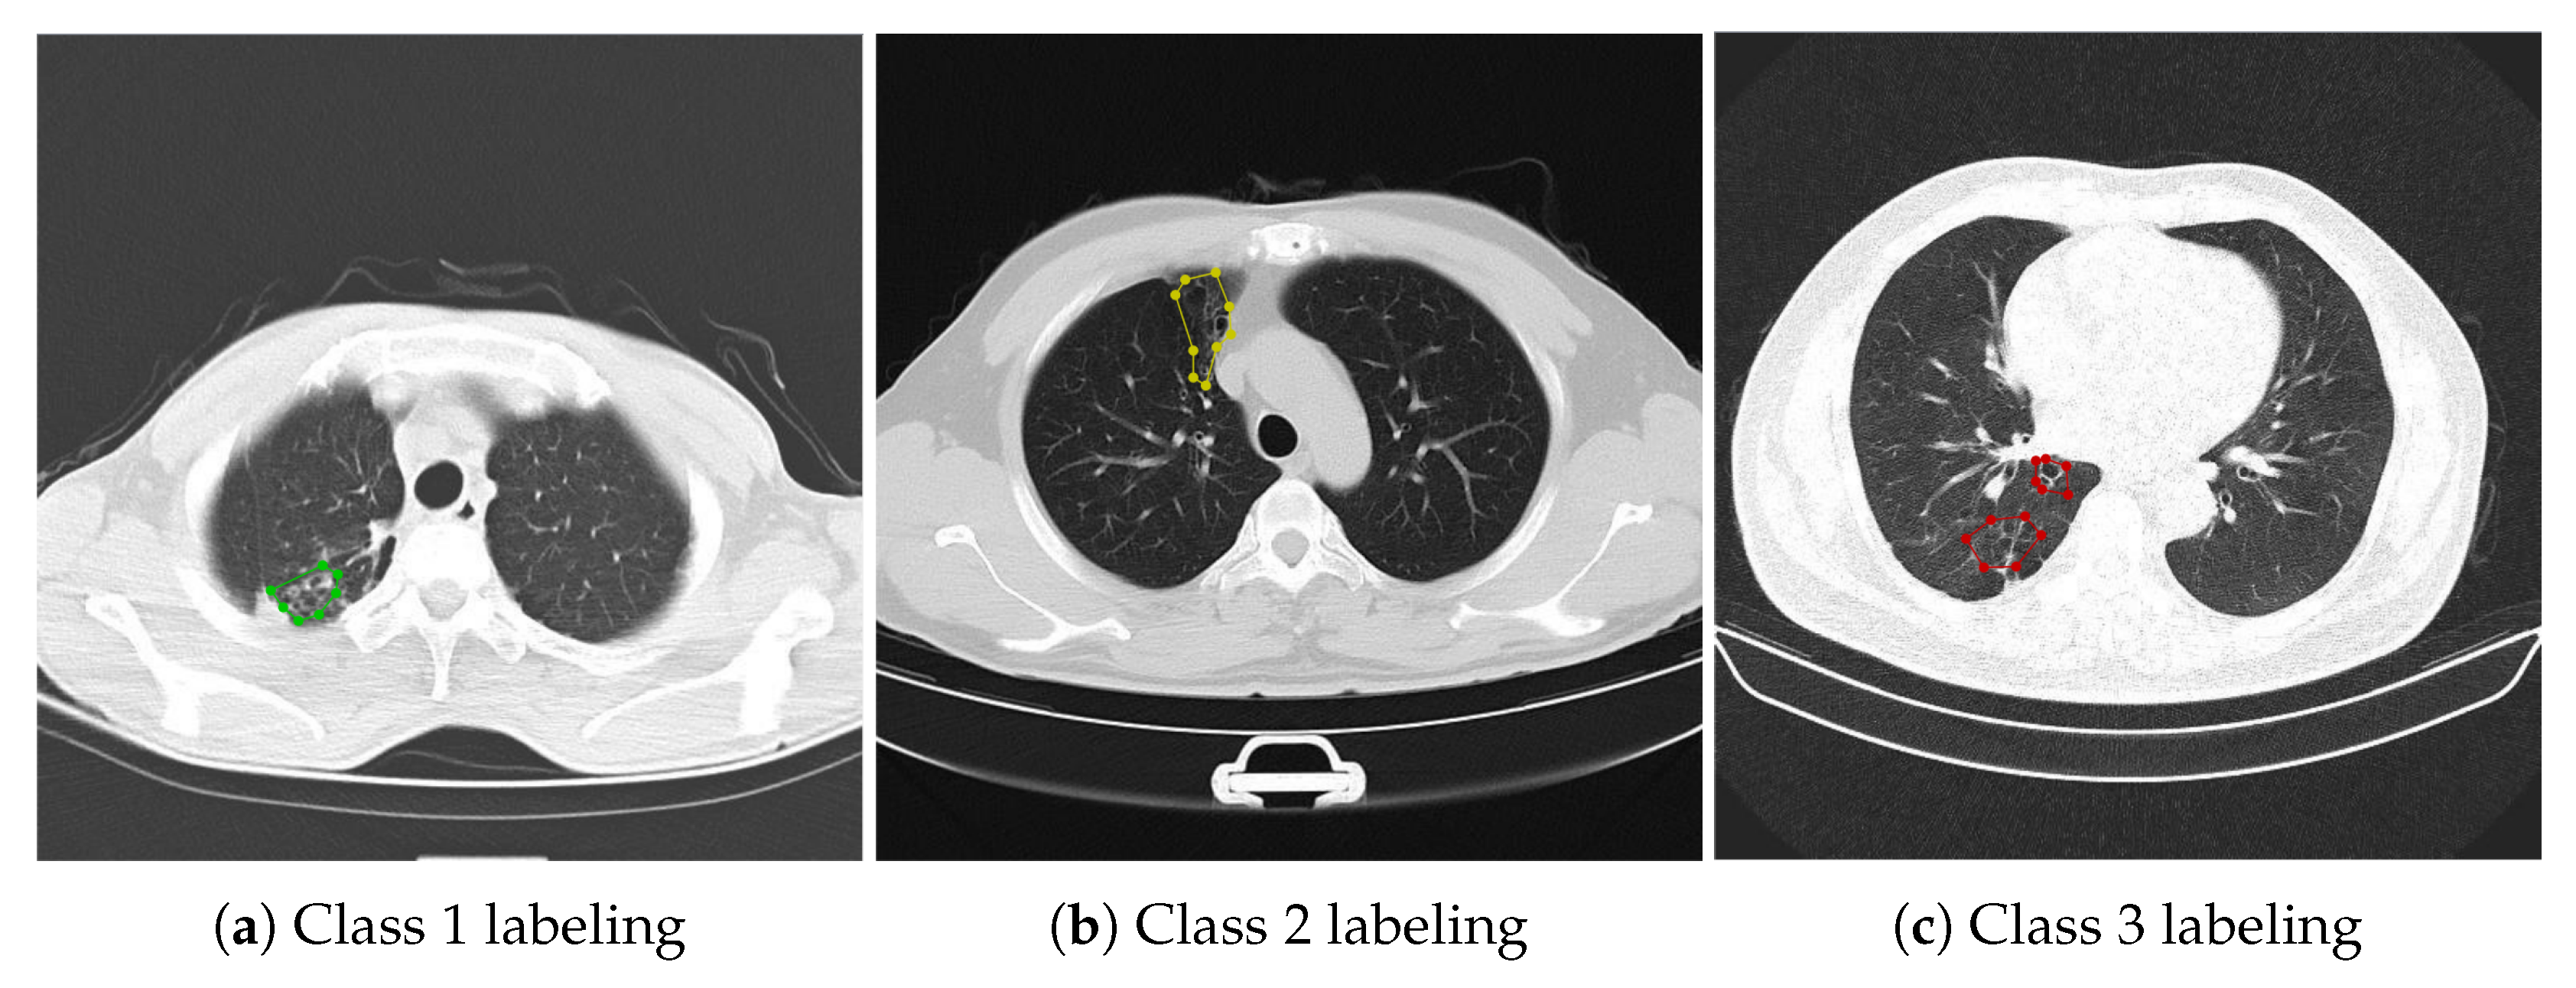

Finally, an experiment was designed to compare the detection and classification effects of HDC Mask R-CNN model and original Mask R-CNN model on bronchiectasis. The experimental data set adopts the data set after image enhancement and lung lobe segmentation. Except for different models, the data set, environment, and other parameters remain the same. Figure 11 shows the curve of Loss with the increase in the number of epochs. Table 12, Table 13, Table 14 and Table 15 are Mask R-CNN and HDC Mask R-CNN using the 1-2-5 2-1 structure, compared in the detection specificity, sensitivity, classification accuracy, and detection IOU of bronchiectasis after training on the data set after using ACER for image enhancement and using RDU-Net for lung lobe segmentation. Figure 12 shows the final detection effect of three types of bronchiectasis.

As can be seen from the table, HDC Mask R-CNN is improved to different degrees than the original Mask R-CNN model in terms of classification accuracy, IOU, specificity and sensitivity. In other words, HDC Mask R-CNN can better detect and classify bronchiectasis in processed lung CT images.

The HDC Mask R-CNN model used in this paper has an accuracy of 91.4% in bronchiectasis classification, with a detection IOU of 88.8%, sensitivity of 88.6%, and specificity of 85.4%. It only takes 1 s to detect one image. Under the premise of high accuracy, it has a fast detection speed and high reference value. Compared with doctors’ manual judgment of bronchiectasis on lung CT images, the speed is greatly improved on the premise of the same accuracy, and a large amount of data can be processed quickly and efficiently at the same time. Because of the high accuracy, the identification results can be used as a very useful reference for doctors to distinguish bronchiectasis. Doctors only need to judge the uncertain samples of the model, which improves the efficiency and reduces the burden of doctors. Figure 12 shows the detection and classification results of three types of bronchiectasis obtained by using the research method used in this paper.

Figure 12. HDC Mas R-CNN detection results for three types of bronchiectasis. (a) Class 1 original image. (b) Class 2 original image. (c) Class 3 original image. (d) Class 1 result. (e) Class 2 result. (f) Class 3 result.